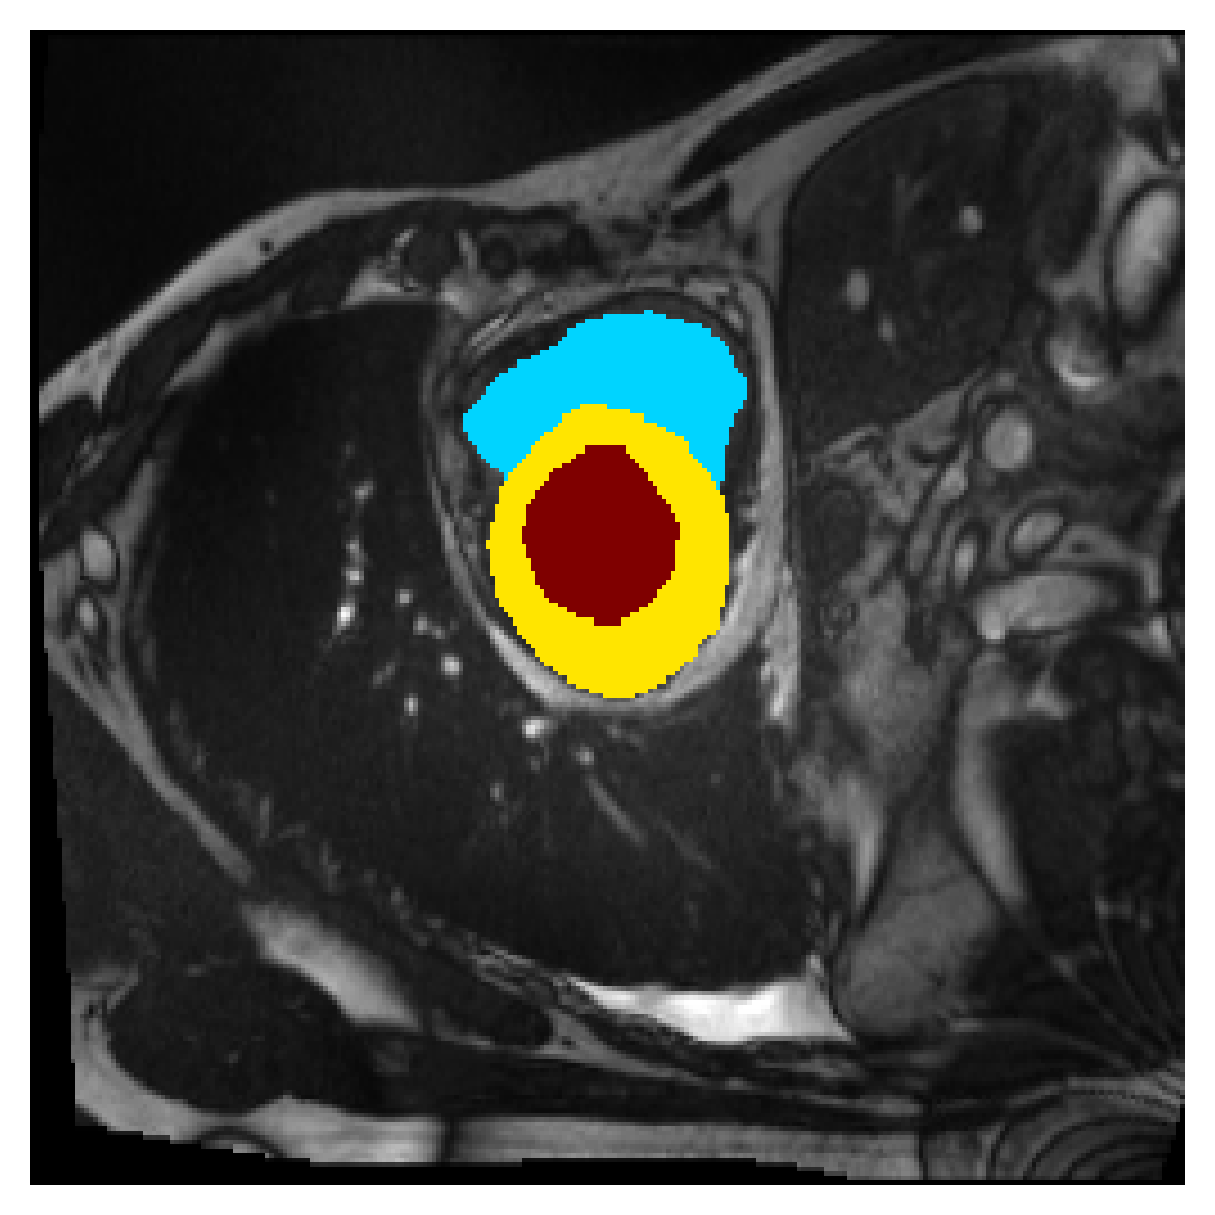

Qualitative comparison

| (a) Ground truth | (b) , full | (c) , weak | (d) |

| (full) | supervision | supervision | |

| (e) | (f) | (g) | (h) CRF-loss |

In Figure 6 we provide qualitative results on a number of randomly chosen test set slices. Upon visual inspection, we can observe that training with the intensity-aware distances (particularly with and ) follows the image gradients better and is better at recovering the underlying shape than the Euclidean version. The CRF-loss seems to recover the shape of the myocardium and left ventricle to some extent, but fails entirely on the right ventricle.